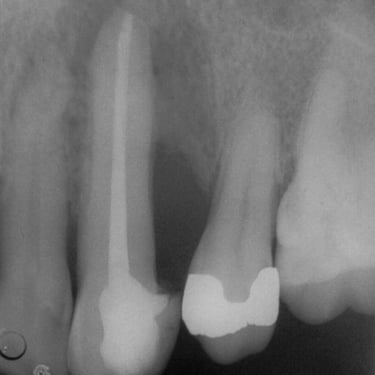

Perforación Radicular

Una perforación radicular es una abertura anormal en la raíz del diente, generalmente debido a un procedimiento dental fallido o una caries profunda.

Los pacientes pueden sentir dolor y notar hinchazón en la encía.

El tratamiento incluye la reparación de la perforación y el tratamiento de conducto. Es crucial reparar la perforación para evitar una infección.